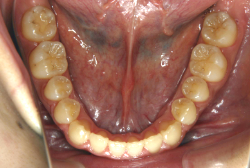

診断の結果、典型的なアングル2級1類の上顎前突です。上下歯列の正中の不一致も見られます。しかし、歯の大きさは平均値に近く、配列の凸凹がそれほど見られません。このまま放置すると、将来的には抜歯を伴う矯正治療を行う可能性が高くなりますが、このタイミングで適切な治療をすると、非抜歯治療が可能かもしれません。

第2段階としてマルチブラケット法を非抜歯で1年間行いました。歯の傾斜が修正され、正中も一致し、美しく機能的な配列に仕上がりました。再診時に確保した隙間をすべて使って、すべての永久歯を理想的な位置に配列することができました。前傾していた上の前歯は真っ直ぐに直立し、完全な正常咬合が確立できています。